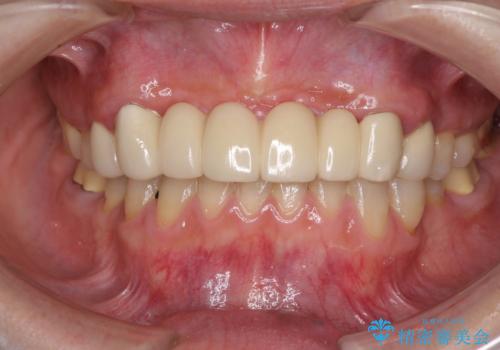

[MTMを行い歯の神経を保存] 歯周補綴ブリッジ

![[MTMを行い歯の神経を保存] 歯周補綴ブリッジの症例 治療後](https://seimitsushinbi.jp/wp/wp-content/uploads/2021/04/75330aaa19199048b71f28658fe46b5b-1-500x350.jpg?v=1618452202)